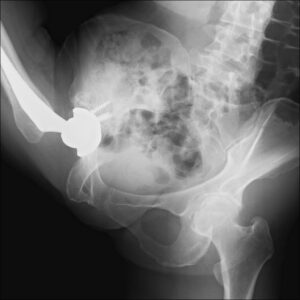

X線透視装置台でY字バランス

患者さんにご協力いただき、X線透視装置台の上でさまざまなバレエのポーズを取っていただいたところ、脱臼を懸念させるような動きは生じえないことがはっきりと観察できました。筋腱完全温存手術によって温存された筋肉が股関節の過度な動きを制限し、骨盤本来の動きが加わることで、大きな可動域を生み出していることが改めて認識できたわけです。